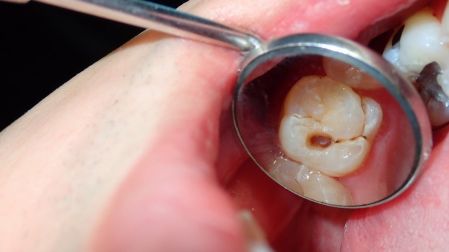

Las caries son una enfermedad dental común que afecta a los dientes. Son causadas principalmente por la acción de bacterias presentes en la boca, especialmente Streptococcus mutans. De acuerdo con información del Instituto Médico Cleveland Clinic, las caries son cavidades oscurecidas que se forman en la superficie de los dientes.

Encontrar una cavidad oscura o de color marrón en los dientes puede ser una de las primeras señales de caries, pero no la única. El mal aliento, la sensibilidad dental ante los alimentos o bebidas frías y/o calientes, así como el sangrado en las encías también podrían revelar que tienes caries. De ahí la importancia de cepillar adecuadamente los dientes y acudir con tu dentista.